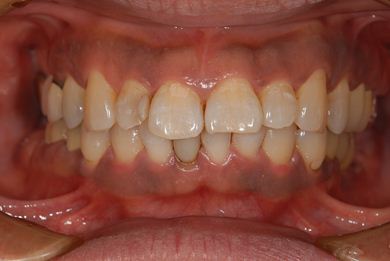

インプラントの症例写真 IMPLANT

インプラント治療+セラミック治療

| 治療内容 | インプラント2本、メタルボンドセラミッククラウン7本(メタルボンド用土台5本)、歯肉歯槽骨整形手術 | ||||||||||||||||||||||||||||||||

| 総治療費 | 1,401,435円 | ||||||||||||||||||||||||||||||||

| 治療期間 | 11ヶ月 |